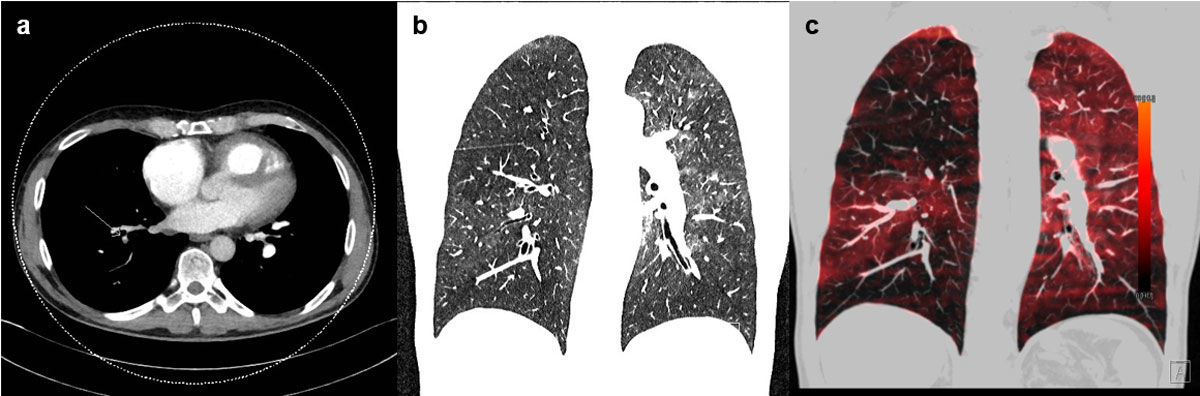

The introduction of dual-energy CT (DECT) (fig. 11) permits functional data on lung perfusion (iodine distribution maps / lung perfusion blood volume images) in addition to anatomical images [58]. With the processed data, the following images can be generated: conventional grey-scale images, colour-coded overlays that highlight the iodine distribution, and virtual nonenhanced images from post-contrast images by use of iodine-subtraction techniques [43]. These are reader-independent and rapid tools to quantitatively assess regional iodine density, reflecting pulmonary perfusion, and correlate with a V/Q scan or single photon emission computed tomography (SPECT) V/Q scan [62, 63]. Qualitative assessment of less- or under-perfused lung areas is comparable to scintigraphy [43, 64, 65], and might replace V/Q scans in the future.

Figure 11 Dual-energy computed tomography (CT). (a) Contrast-enhanced CT axial reconstruction demonstrating a dilated right atrium, and narrowing of the pulmonary arteries of the right side by thromboembolic material; (b) contrast-enhanced CT coronary reconstruction with mosaic perfusion pattern; (c) dual-energy CT scan showing iodine mapping of unmatched perfusion defects. (Courtesy of Prof. T. Frauenfelder.)